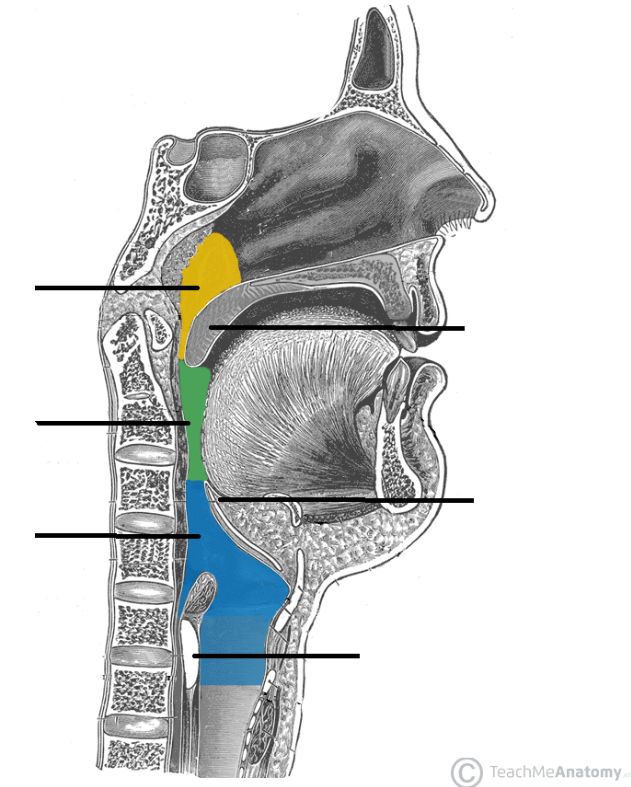

Nasopharynx

yellow highlight

Oropharynx

green highlight

Laryngopharynx

blue highlight